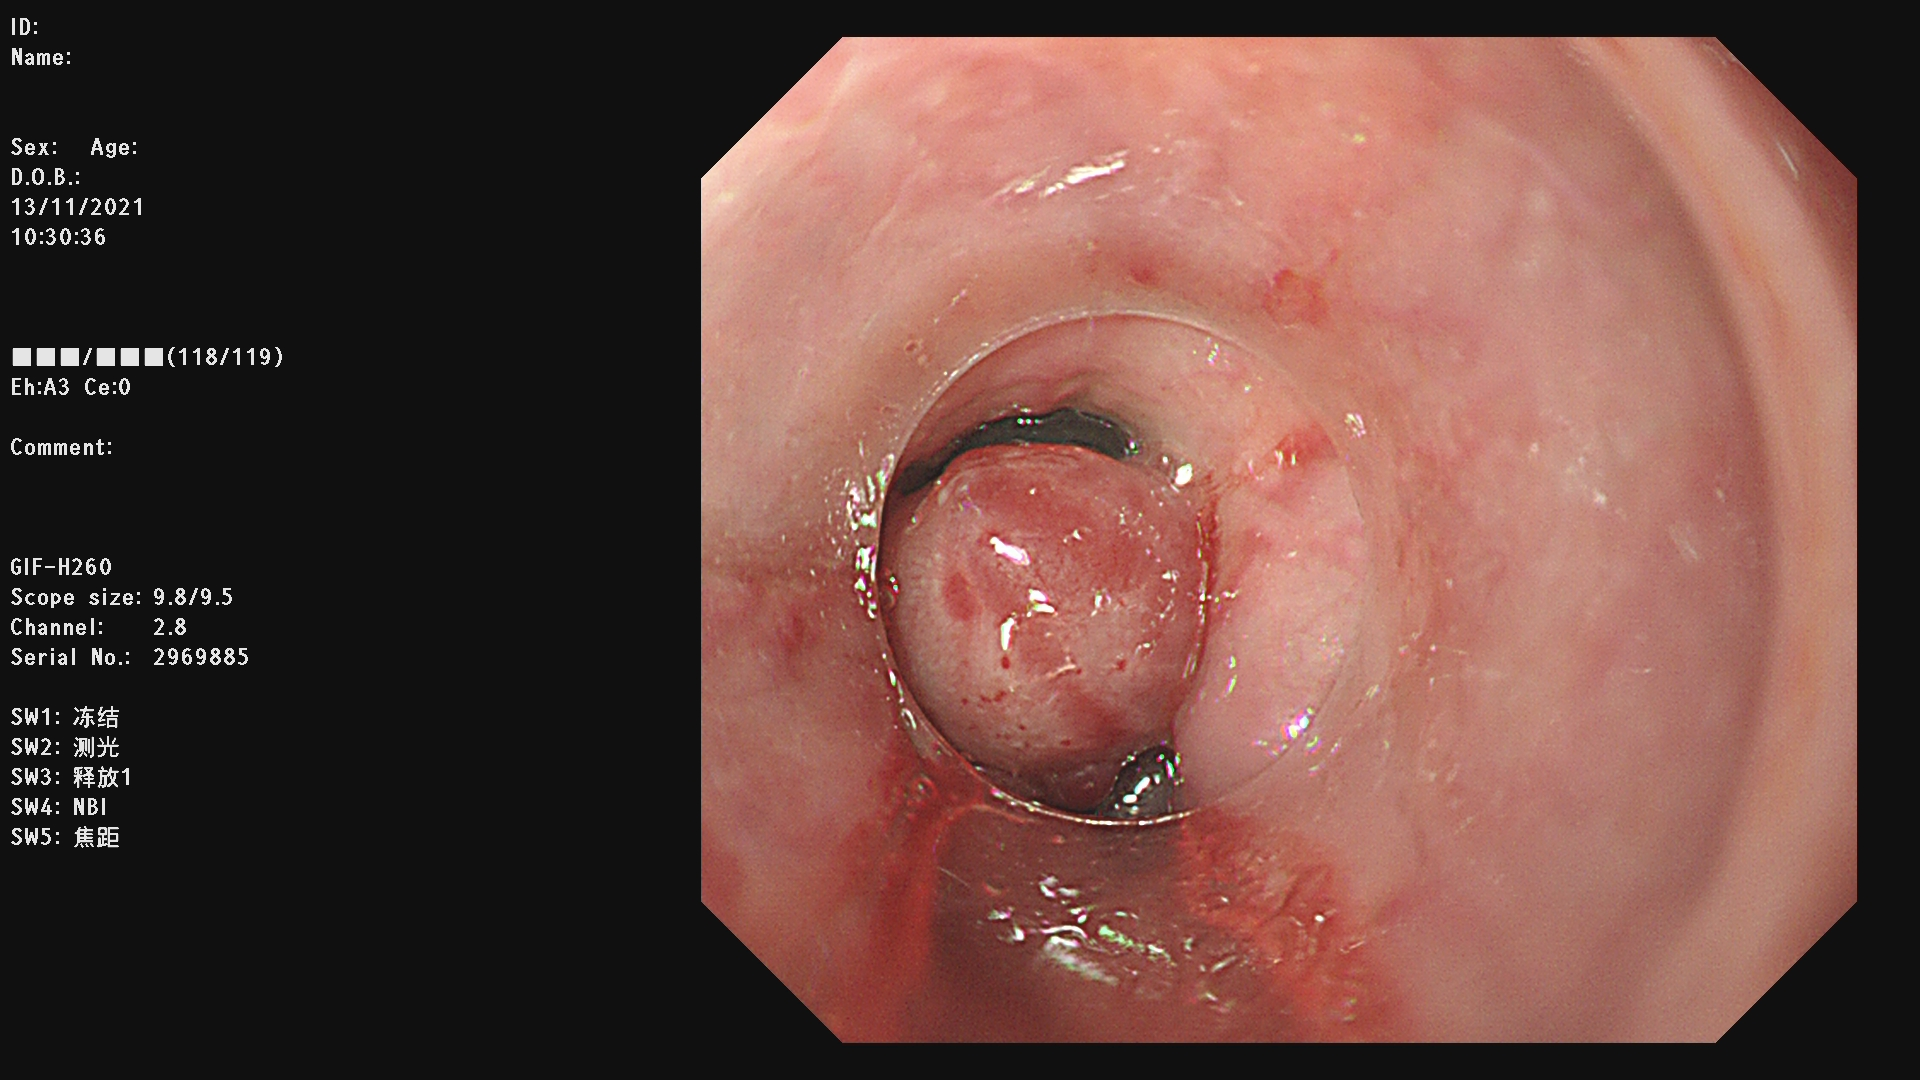

内镜下食管静脉曲张套扎术简称EVL,是一种安全有效的治疗食管静脉曲张破裂出血以及预防出血的方法。EVL具有操作简便、创伤小、安全性高,疗效确切、可重复进行的优点。

内镜下硬化术(EIS)是通过内镜下注射硬化剂和/或组织胶治疗急性食管胃底静脉曲张破裂出血及预防再出血的方法。

例一 :